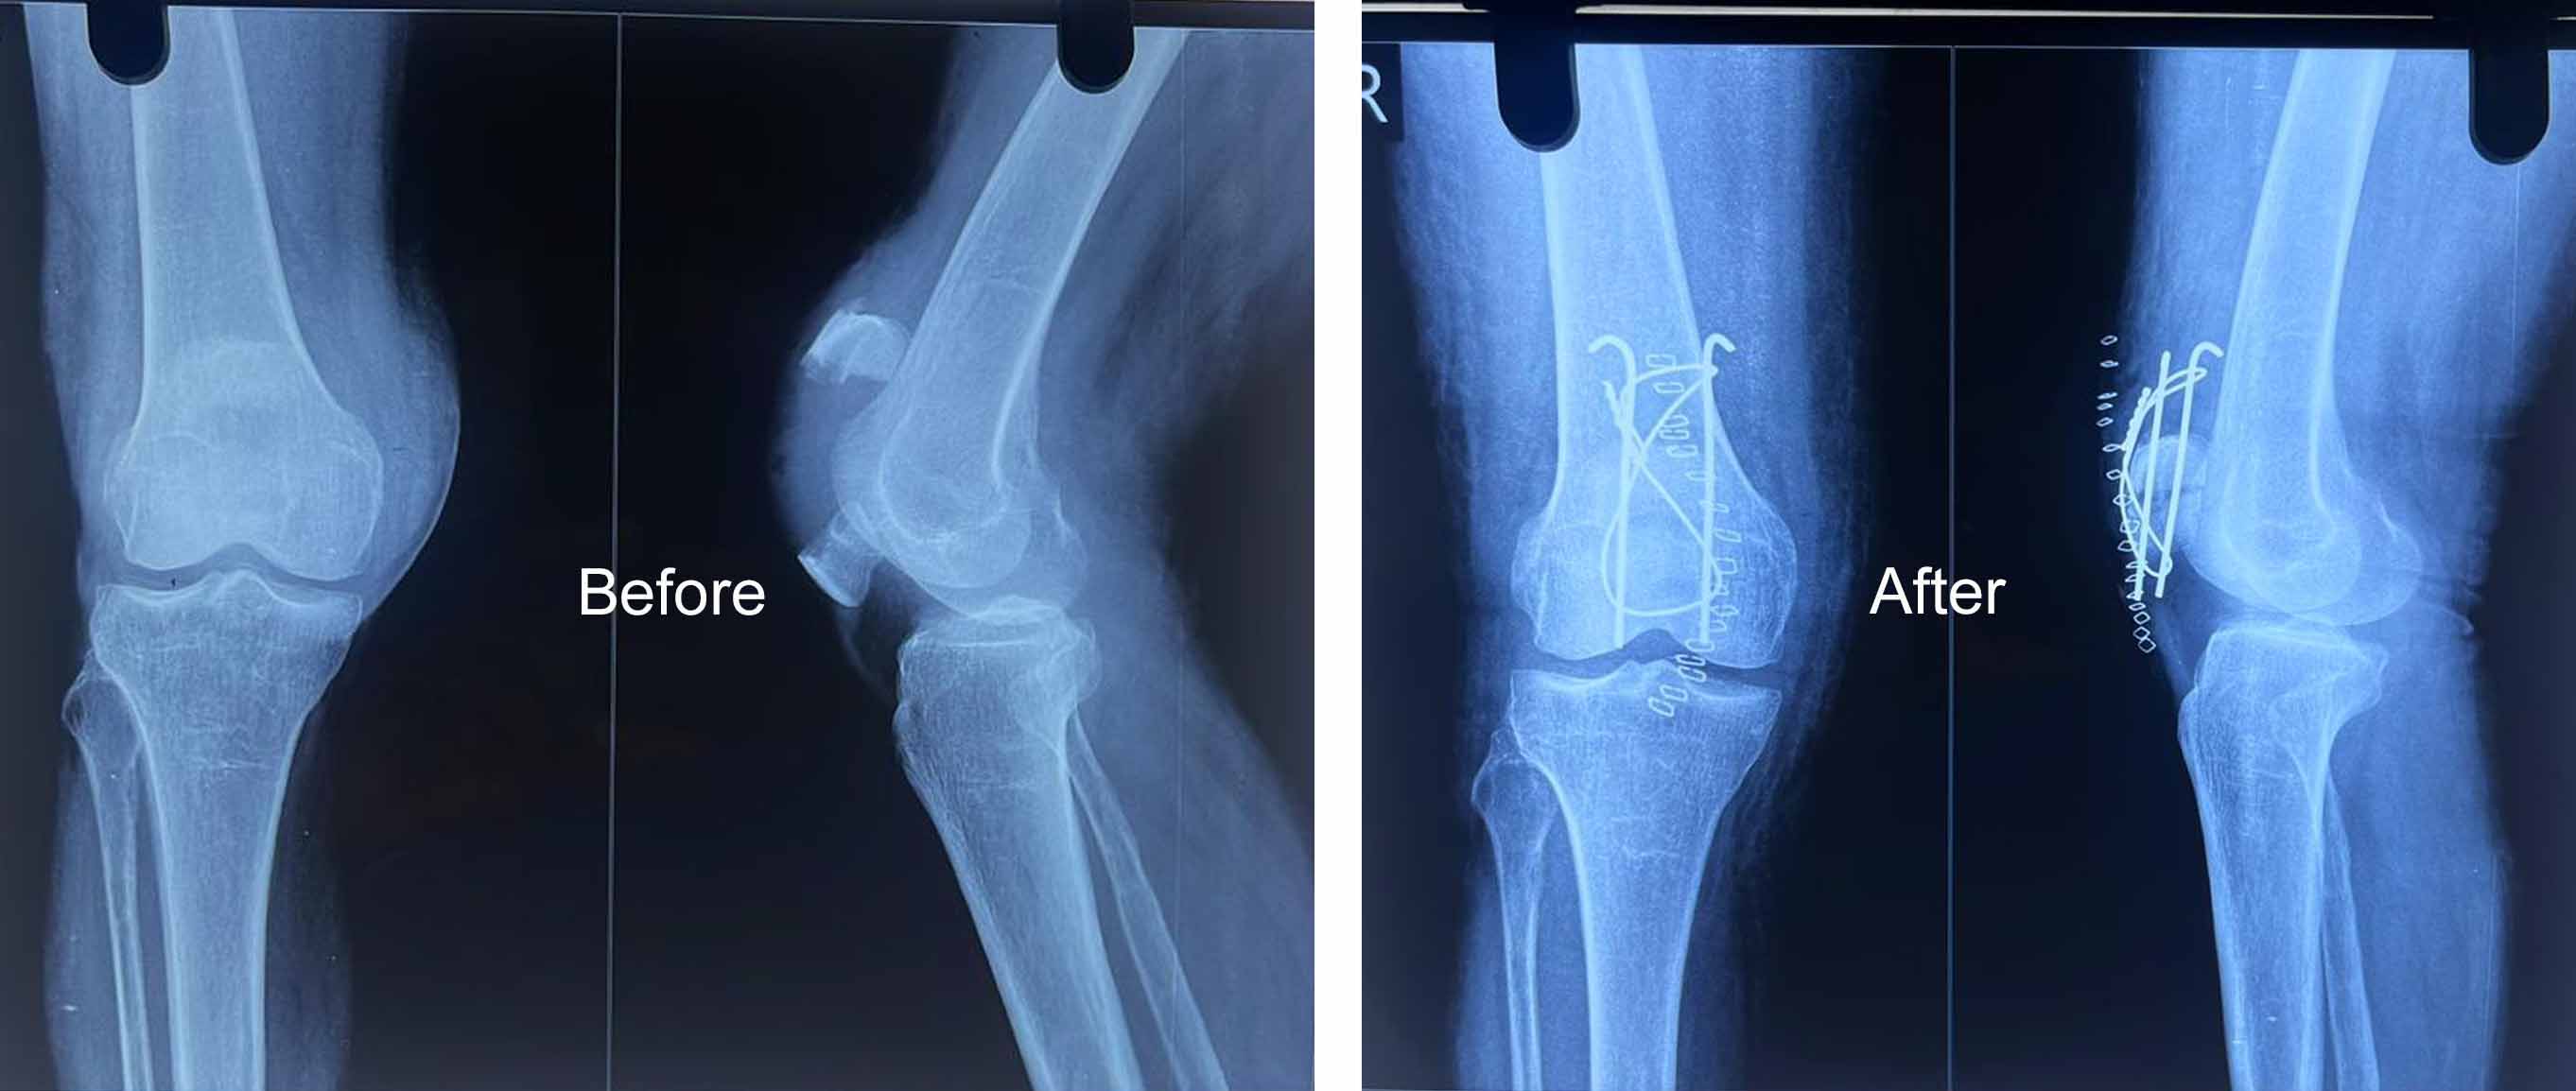

Orthopedic Care